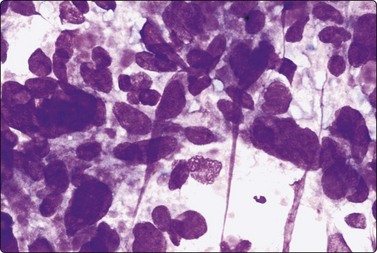

Tumor cells show uniform enlargement with dense cytoplasm and well-defined cell borders. INCIs (Fig. 6.35), characteristic of PC, are seen in up to 90% of cases. They are seen in 5% of the cells (10% if examined under oil immersion under 2–3 planes of focus).164,165 INCIs, however, are not specific to PC as they can be seen in atypical adenomas,166 hyalinizing trabecular tumors,167 MC (see Fig. 6.55),168 AC (see Fig. 6.59) and rarely in FC,90 HT18 and juxta-thyroidal neoplasms (parathyroid adenoma, paraganglioma, etc.).67,90

INCIs have sharp, well-defined, membrane-like margins and are not optically clear but resemble the cytoplasmic color and texture. They probably start as trapped cytoplasm in deep nuclear folds (grooves)169 that eventually invaginate into the nucleus at foci of nuclear membrane weakness. Grooves and inclusions do not usually coexist, possibly due to the pressure of the inclusion unfolding the groove and preventing further groove formation.170 Artifacts such as superimposed air bubbles or fat droplets can mimic INCIs both in PAP- and MGG-stained material.27,171 Optically clear vacuoles and poorly defined central areas of pallor (MGG) should not be accepted as inclusions. The clear or ground-glass (‘Orphan Annie’) nuclei seen in tissue sections are represented in smears by very fine, powdery nuclear chromatin,164 an important diagnostic criterion and a feature best appreciated in ethanol-fixed, PAP-stained smears (Figs 6.35 and 6.36).

Irregular nuclear shapes, convolutions (Fig. 6.35B) and longitudinal nuclear grooves or creases (Fig. 6.36) are visible in cytologic smears (in 85–100% cases) and in sections.165,170 Grooves are obvious in alcohol-fixed material but are difficult to discern in MGG preparations. Strict criteria for recognition have been suggested: continuous grooves or creases, clearly defined and running the length of the nucleus.172 The presence in ≥20% of cells, as counted in selective fields where grooves are frequent, is highly predictive of PC.173 Grooves, however, may be found in small numbers in 70–80% of non-papillary neoplasms, in 50–60% of non-neoplastic thyroid lesions172 and in a variety of extrathyroid tumors; hence, metastatic carcinoma and melanoma are included in differential diagnoses.42

image

Fig. 6.36 Papillary carcinoma

Sheet of cells with large, very pale (but not optically clear) crowded nuclei; powdery chromatin; many longitudinal grooves (Pap, HP oil).

Tumor cells often show delicate soap-bubble like cytoplasmic vacuolation (septate cytoplasmic vacuoles)174or squamoid cytoplasm (metaplastic cells). Dense cytoplasm and well-defined cell margins may simulate Hurthle cells (Fig. 6.37) or squamous cells (Fig. 6.38A). True squamous metaplasia and Hurthle cell change may be present. Cells with abundant vacuolated cytoplasm are seen (Fig. 6.38B) resembling histiocytes (foam cells) but with nuclear features of PC.162 Such ‘foam cell metaplasia’ is seen in about 50% of PCs and is best appreciated at the edges of the smear.42 Foam cell metaplasia may also be seen in cystic NG with papillary hyperplasia42 and in papillary breast lesions. Macrophages and cell debris may be prominent, especially when cystic change is present. Multinucleate giant cells are frequently seen and, if numerous, have been shown to be associated with larger tumor size and greater likelihood of extrathyroidal extension.175 Lymphoid cells are present in 30% of cases.176